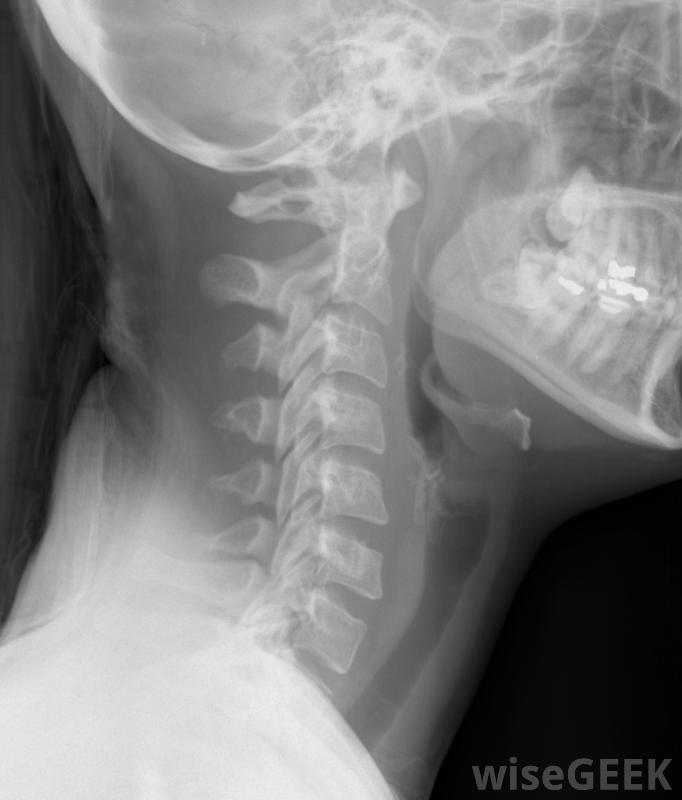

当颈椎或颈部持续疼痛无法用其他方法成功治疗时,有时需要进行颈椎融合。这种手术将颈部的椎骨相互融合,限制运动,从而减轻或消除疼痛。有时,颈椎融合术是结束长期疼痛的最佳方法颈椎的慢性疼痛通常是由神经压迫引起的,在神经受压处融合椎体,可大大减少该区域的活动,也有助于为神经和神经根留出额外的空间,其结果是减轻受影响神经的压力,这样可以减轻甚至消除疼痛。

颈椎融合术可以作为椎间盘突出治疗的后续措施根据患者个人的需要,颈椎融合术有不同的方法,这种手术是在颈前切口进行的,称为颈椎前路融合术,也可以通过颈部后部进行,这种手术就是颈椎后路融合术手术本身包括切除椎骨之间的椎间盘或整个椎骨,然后在剩下的椎骨之间放置一块植骨块,它将生长到上下两块骨头中,有效地将它们融合在一起。其他的颈椎融合方法包括使用金属植入物或钢板或使用人工融合材料。骨移植通常取自患者,通常来自髋骨,但也可以使用尸体上的骨头颈椎融合术后,颈部活动有所减少,但这通常对患者的整体活动性影响不大。作为疼痛治疗,该手术在大多数情况下是成功的。术后有时会出现并发症,需要后续手术接受该手术的患者在康复期间通常必须住院一段时间,然后必须戴上短时间的颈领,以便在愈合过程中保持颈部不动。